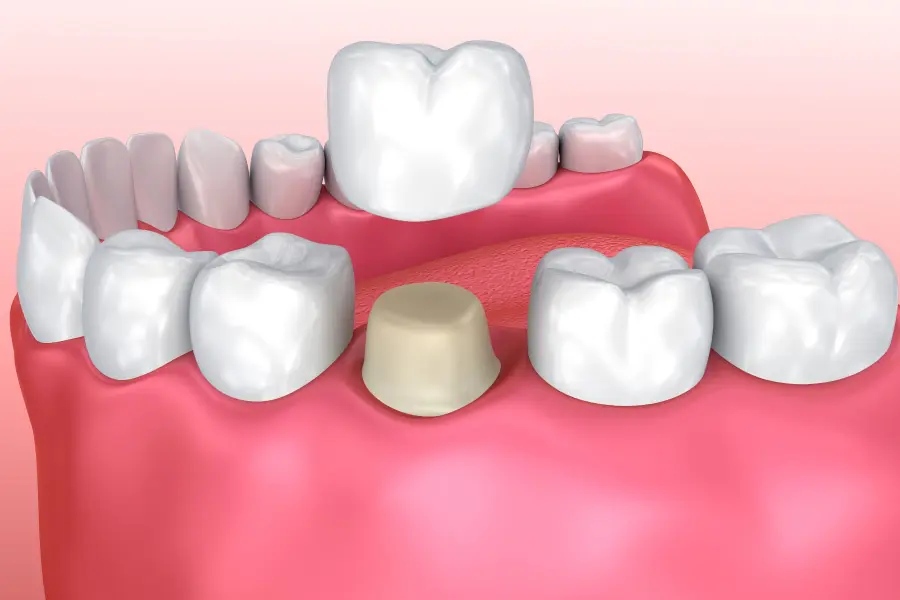

A dental crown is a custom-made cap designed to encase the entire visible portion of a damaged or weakened tooth. Crafted from premium materials like ceramic, zirconia, E-max, composite resin, or metal-infused porcelain, crowns restore not only the form and appearance of natural teethbut their full function, too.

Step 2: Tooth Preparation

Step 3: Fabrication (In-Lab or In-Clinic)

Step 4: Fitting & Bonding